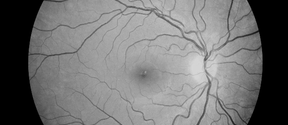

retina

NeuroEye Insight

Non-invasive approach by analyzing retinal scans with advanced AI algorithms to identify early indicators of Alzheimer’s, thereby offering a transformative solution for early detection.

Maculaser

Maculaser’s pioneering retinal treatment triggers the natural healing response of senescent cells with personalized heat exposure. Targeting disease prevention, we offer a patient-specific, non-damaging solution to retinal disorders affecting millions worldwide.